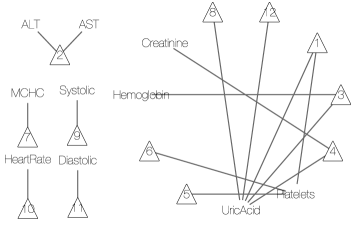

As a comparison with results under alternative approaches, we consider inference under SLFM, applied directly to the blood test results, without converting to binary or ternary symptoms. The tuning parameter was set to 1 to approximately match the number of latent diseases found by DFA. SLFM implements inference on sparse symptom-disease relationships as shown in Figure 8(b). Although there is no known truth for symptom-disease relationships, it is difficult to interpret certain links. While uric acid may play some role in certain diseases, we do not expect it to be related to 5 out of 12 latent diseases. In addition, both latent diseases 5 and 6 are related to platelets only, which should be collapsed into one disease. We also ran LSFM with larger but found similar results. For example, when , SLFM identifies 20 latent diseases, 17 of which are associated with uric acid. These somewhat surprising results may be due to the assumption of normality and linearity of SLFM, and taking no advantage of prior information.

Next we apply SLFM to the EHR data that are scaled and centered at the midpoint of each reference range. Choosing , the algorithm found 10 latent diseases whose relationships with symptoms are depicted in Figure 8(c). Some findings are consistent with ours. For example, disease 3 here is similar to disease 1 from DFA. Both are related to LDL and TC. Likewise, disease 2 is similar to disease 4 from DFA. But some findings remain difficult to interpret. Six diseases are associated with only one symptom. For instance, disease 10 is linked to only MPV. However, high or low MPV alone is not of any clinical importance. It is only of concern if other platelet-related measurements are also out of their normal ranges. This synergy is well captured by DFA (via disease 3).